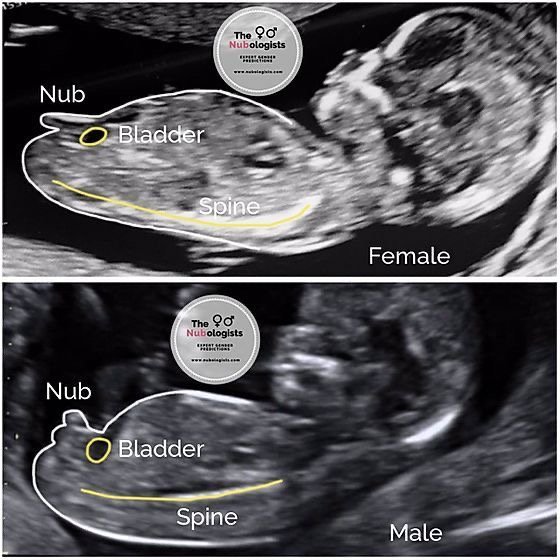

Момичета, вярно ли е , че и при момичетата , и при момчетата има издутинка в началото? В 11 г.с се вижда лека такава, но без тестиси всеки още. Като всеки човек, любопитна съм за пола - без огромни предпочитания , наистина искам да е здраво и мисля главно за предстоящата морфология и скрининг.

dreamer1992 вярно, гледах даже снимчици в интернет. Ще прикача тук да сравняваш с твоите 😅Ако откриеш пола самичка би било супер яко. Аз сравнявах, но не съм 100% сигурна какво виждам. Ориентирай се за местоположението по пикочния мехур. Той трябва да се вижда ясно ❤